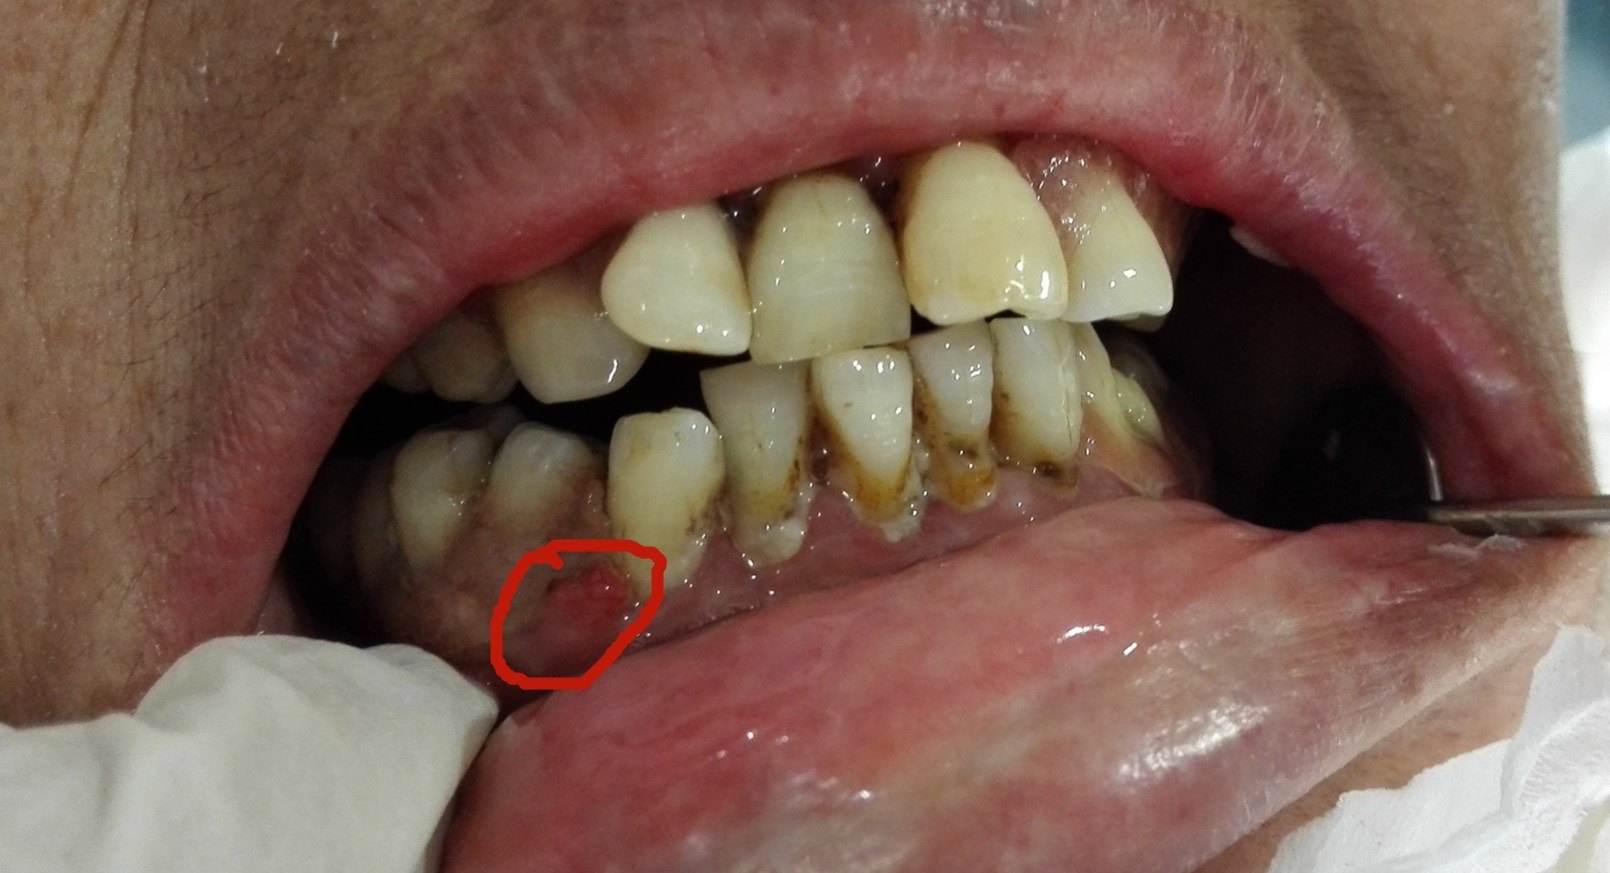

4、冠周炎

这种多由于智齿无法正常萌出引起的,通常表现为牙龈红肿、疼痛,部分人还会出现脸部肿胀、发烧等情况。

建议:反复发炎的智齿,建议 及时拔除。